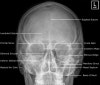

3) Adult Facial Bones - Occipitomental(Waters) 30º View

(2) McGrigor-Campbell lines

| Red line Passes through the zygomatico-frontal sutures and across the upper edge of the orbits Orange line Follows the zygomatic arch, crosses the zygomatic bone and follows the inferior orbital margins to the opposite side Green line Passes through the condyle (1) and coronoid process (2) of the mandible and through the lateral and medial walls of the maxillary antra on each side Midline Used to assess symmetry |